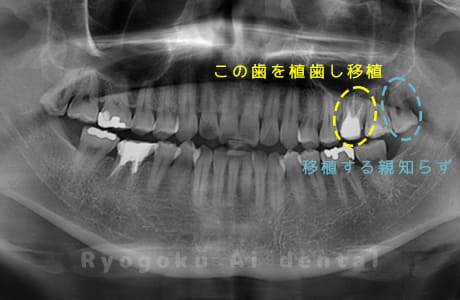

他院で右下の根の治療を行い、セラミックを被せる説明をされていたが、根の治療が終わらないため転院された患者さんです。隣の親知らずの抜歯の必要性と、根の治療を行なっている歯牙の予後が悪いため、移植治療を提案し、右下の親知らずの抜歯と同時に、右下の奥歯(7番)への移植治療を行いました。被せ物を行う必要もなく、順調に経過してます。